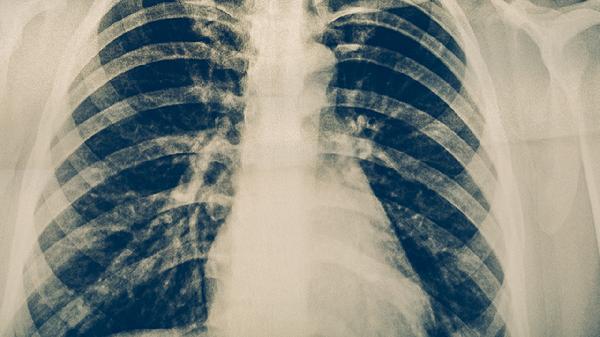

如何清洁肺部?

正常情况下,戒烟、多喝水、远离环境污染等方法可以使肺部清洁,对身体健康也有好处。